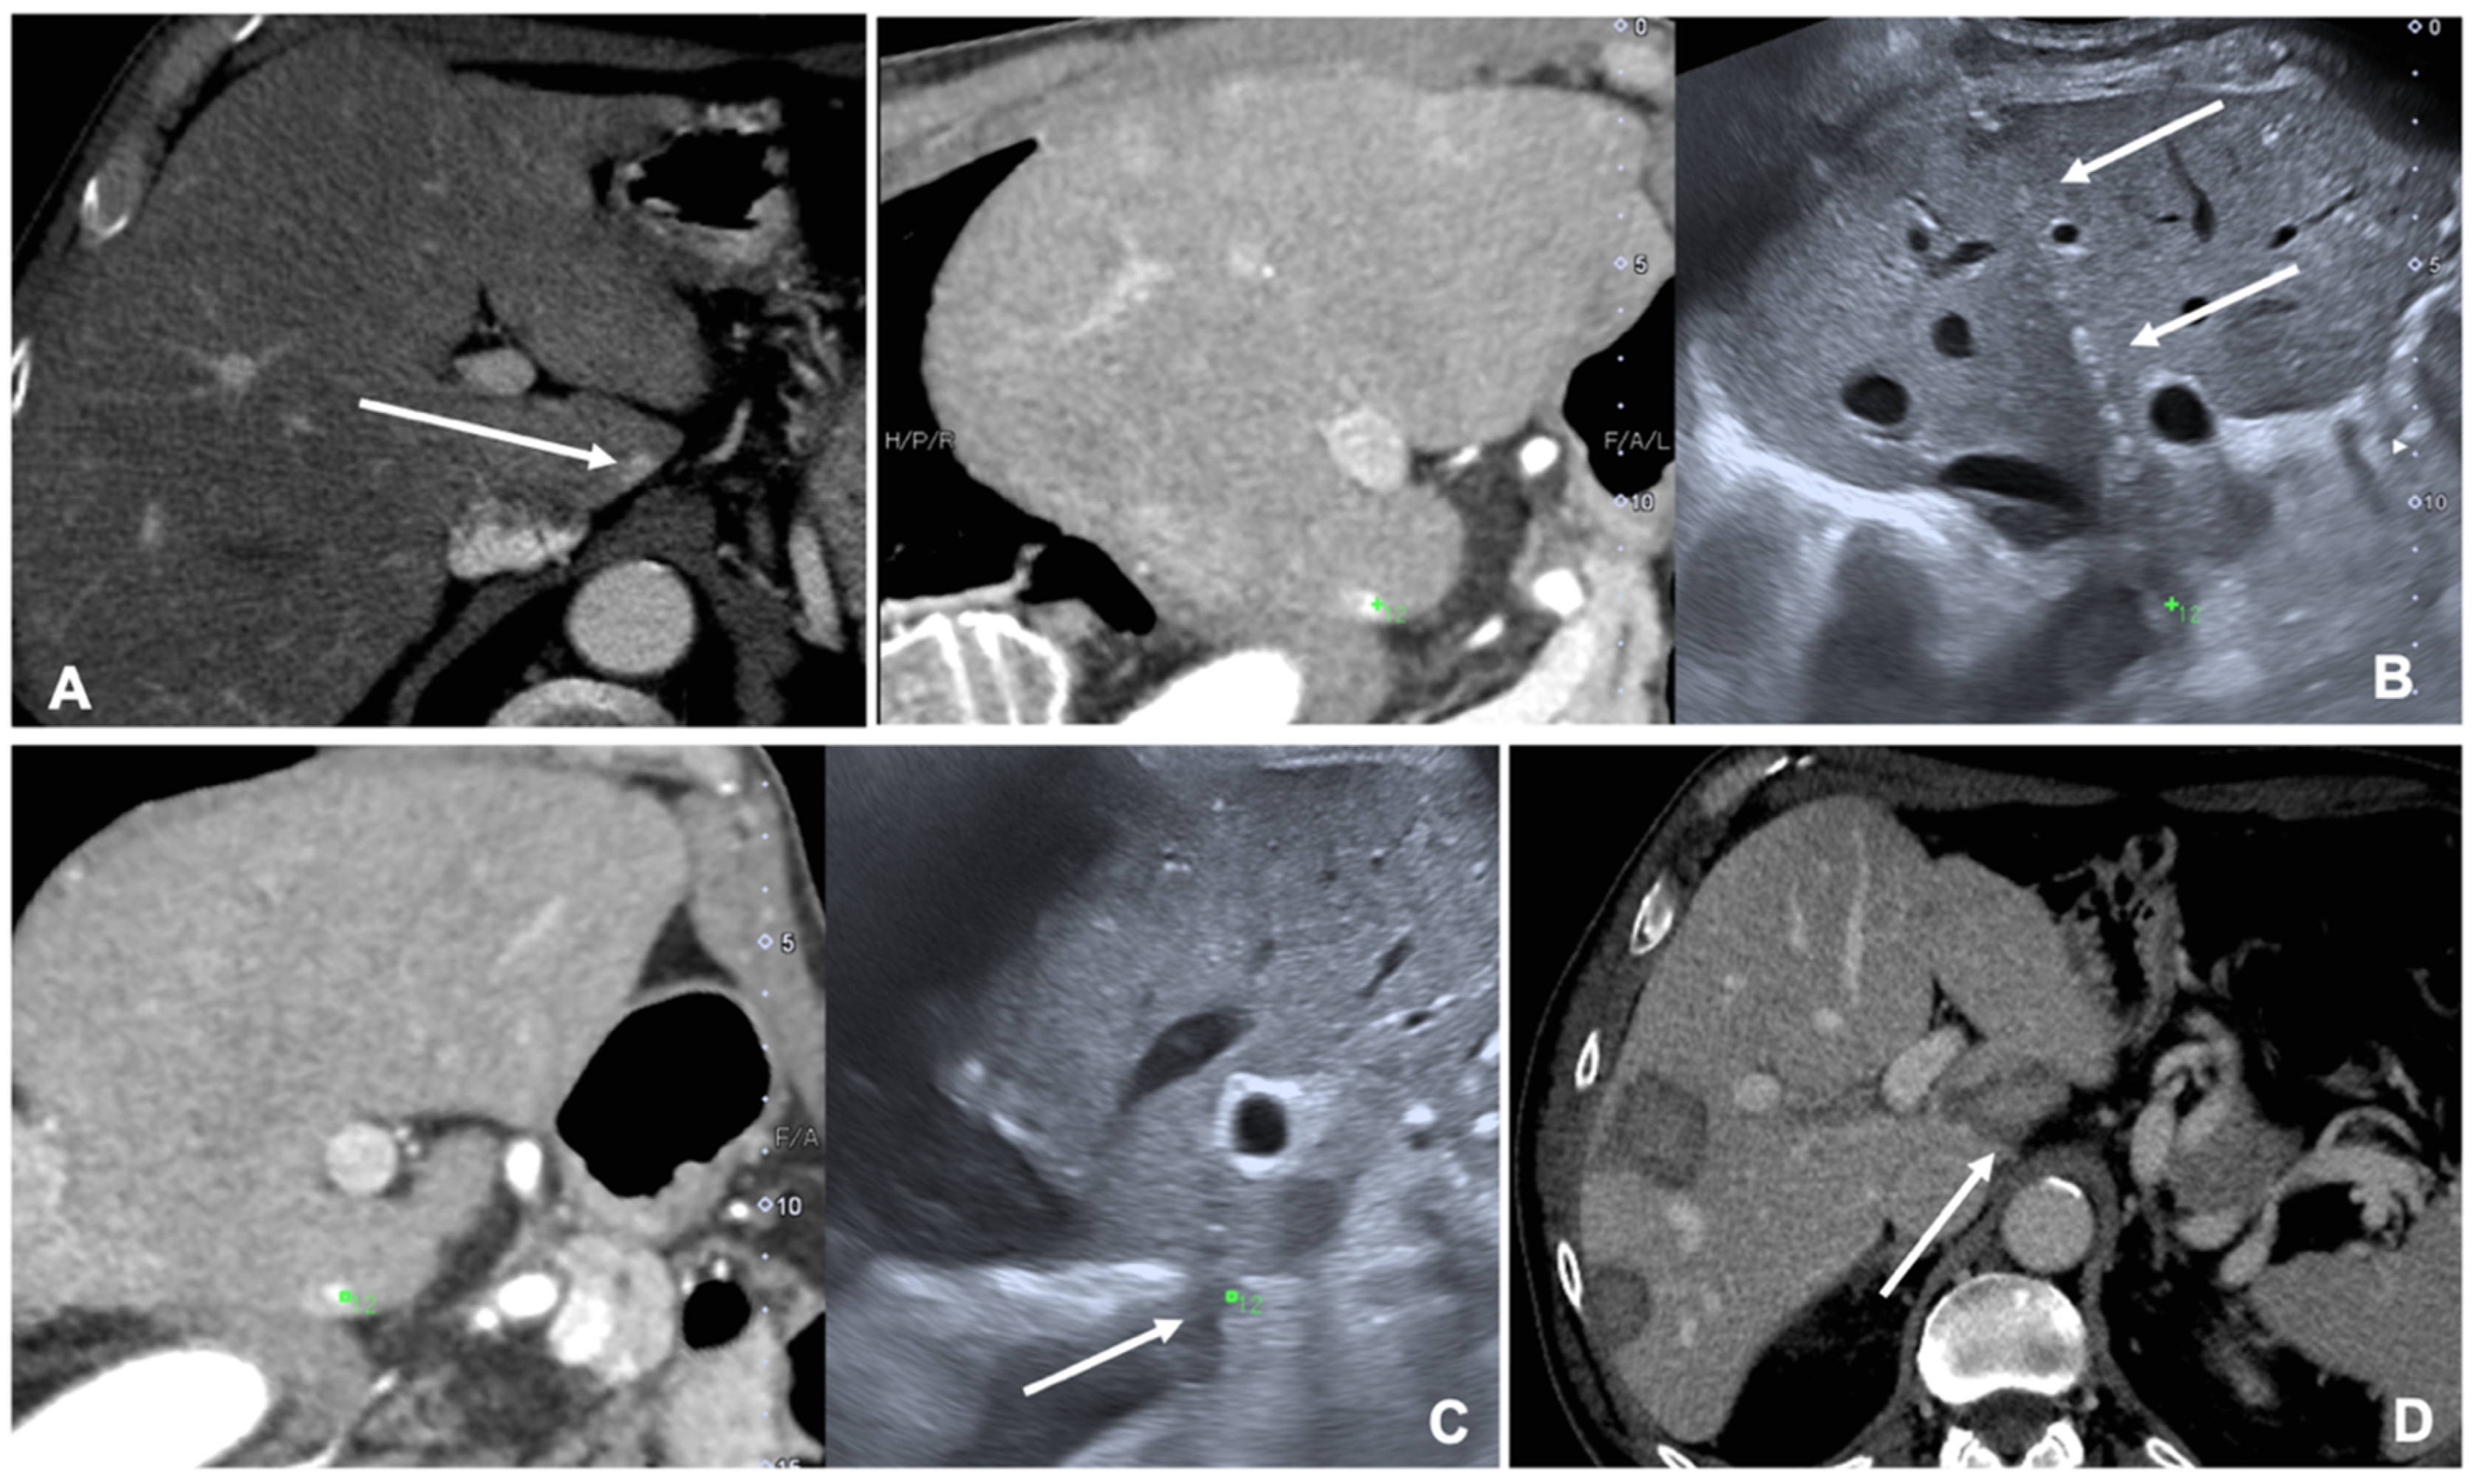

MRI and CT are both used as reference data set for FI; FI imaging with conventional US and liver CT/MR images improves the detection rate of HCC of 45% and, therefore, the procedure’s feasibility after FI [14,20]. However, some studies have shown the superiority of MRI with hepatobiliary phase to CT images for the identifications and definitions of hepatic lesions, especially in small lesions less than 1 cm [21]. Nevertheless, very promising preliminary data are available regarding US/Cone beam CT (CBCT) FI [22]. It is technically feasible and appears to be an effective image guidance modality for achieving correct targeting and ablation of small lesions not clearly visible at US (Figure 2).

Figure 2. Case of a patient with liver metastases from renal cancer treated with microwave ablation (MWA). (A) Axial view during portal phase of the preoperative contrast enhanced Computed Tomography (CECT) showing a 6 mm enhancing lesion of segment I (white arrow); (B) Live multiplanar reconstruction of the same source CT (left side) using fusion imaging (FI) with intraoperative ultrasound (right side). In both views target lesion is marked by a green spot while the MWA needle is marked by two solid arrows in the ultrasound image (right). (C) FI during MWA of the lesion in the liver segment I. Arrow points out the area of gas formation at the tip of the ablation needle. (D) An axial view of the CECT control the day after the procedure. Arrow points out the area of ablation of the liver segment I.